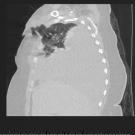

Alexandra Close, BS; Maaria Chaudhry, MS; Kirill Alekseyev, MD; Bilal Chaudhry, MD

A 60-year-old woman presented to the emergency department with blunt thoracic trauma after a head-on motor vehicle accident.